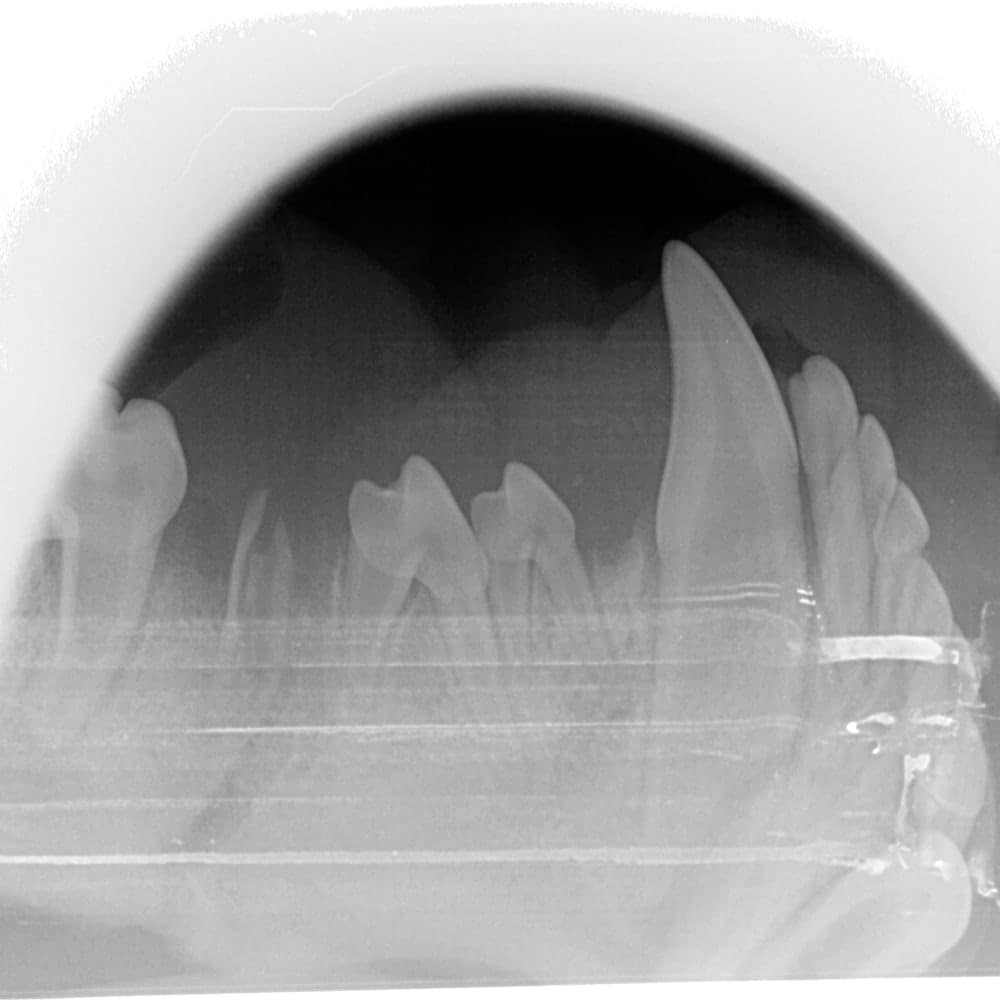

CR (Computed Radiography): The Indirect System

Indirect systems (indirect digital, computed radiography), or CR, use photostimulable phosphor plates to capture the image. These plates are available in several sizes (0, 1, 2, 3, 4, 5) and are about the thickness of a playing card.

These plates must be placed in protective plastic sleeves. Manufacturers recommend using a new sleeve for each EXPOSURE, although they can be reused a few times. Some brands of sleeves need to be torn in the center to be developed, making them unusable a second time. Although phosphor plates are less expensive than digital sensors (about $150 for a size 2 plate and $600 for a size 4), the cost of the sleeves must be considered. They can cost around $1 each, which increases operating expenses. On the other hand, it is less problematic if a patient bites the plate due to its more affordable price.

Phosphor plates can scratch more easily and delaminate if not cleaned with 99% alcohol. They must therefore be replaced after a few years, unlike digital sensors. The variety of sizes offered by this system is its main advantage: size 0 plates easily fit into the mouth of a 1 kg patient or a small cat. Size 4 plates are very useful for taking fewer shots on a large dog and provide a better overall view.

Sometimes, size 4 plates are used to X-ray small companion mammals – this type of system could be advantageous if you treat these kinds of patients in your clinic. Size 5 plates are sold by representatives but, in my humble opinion, offer little benefit in veterinary medicine. Two plates of sizes 0, 2, and 4 make a good kit for all patients.

Phosphor plates must be developed once exposed. This requires a digital developer placed on a countertop in the dentistry room. Developers can vary in size but consider approximately the size of a toaster. Since the plates need to be developed, there is a slight delay in image processing. Development takes about 30 seconds, during which you can take the next shot with a second plate. However, if a mistake was made during the image capture, it may be more difficult to correct the situation because the plate will have already been removed from the animal’s mouth. More artifacts are possible when using phosphor plates. For example, blood on the cassette will be visible during development.

A double exposure can occur if you forget to develop the plate. The main disadvantage is that the plate could be placed upside down in the patient. Indeed, the blue side of the plate should face the X-ray generator. If the plate is placed upside down, the resulting image will be a mirror image of reality. It would be unfortunate to extract a tooth on the wrong side if you don’t realize this mistake. Indirect systems are often slightly more expensive to purchase than direct systems – unless a sensor breaks!